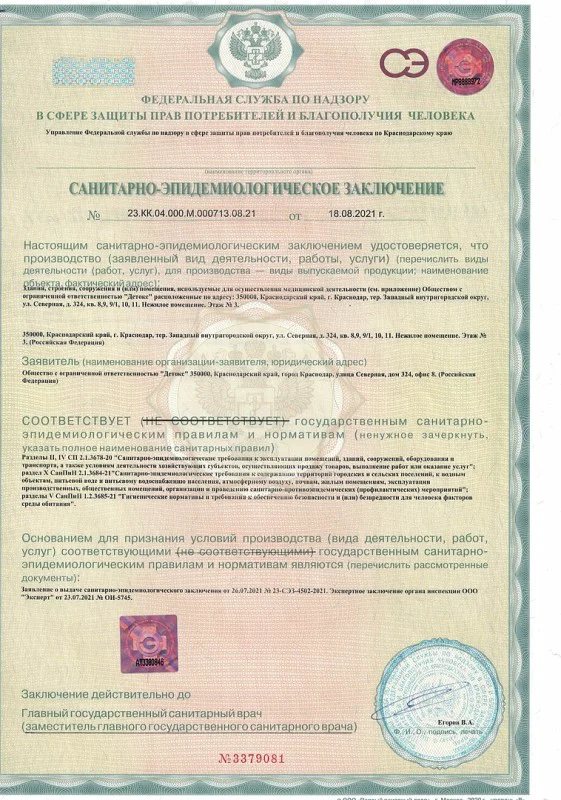

Лицензия на осуществление медицинской деятельности

Лицензия на осуществление медицинской деятельности

Лицензия на осуществление медицинской деятельности

Лицензия на осуществление медицинской деятельности

Лицензия на осуществление медицинской деятельности

Лицензия на осуществление медицинской деятельности

Лицензия на осуществление медицинской деятельности

Лицензия на осуществление медицинской деятельности